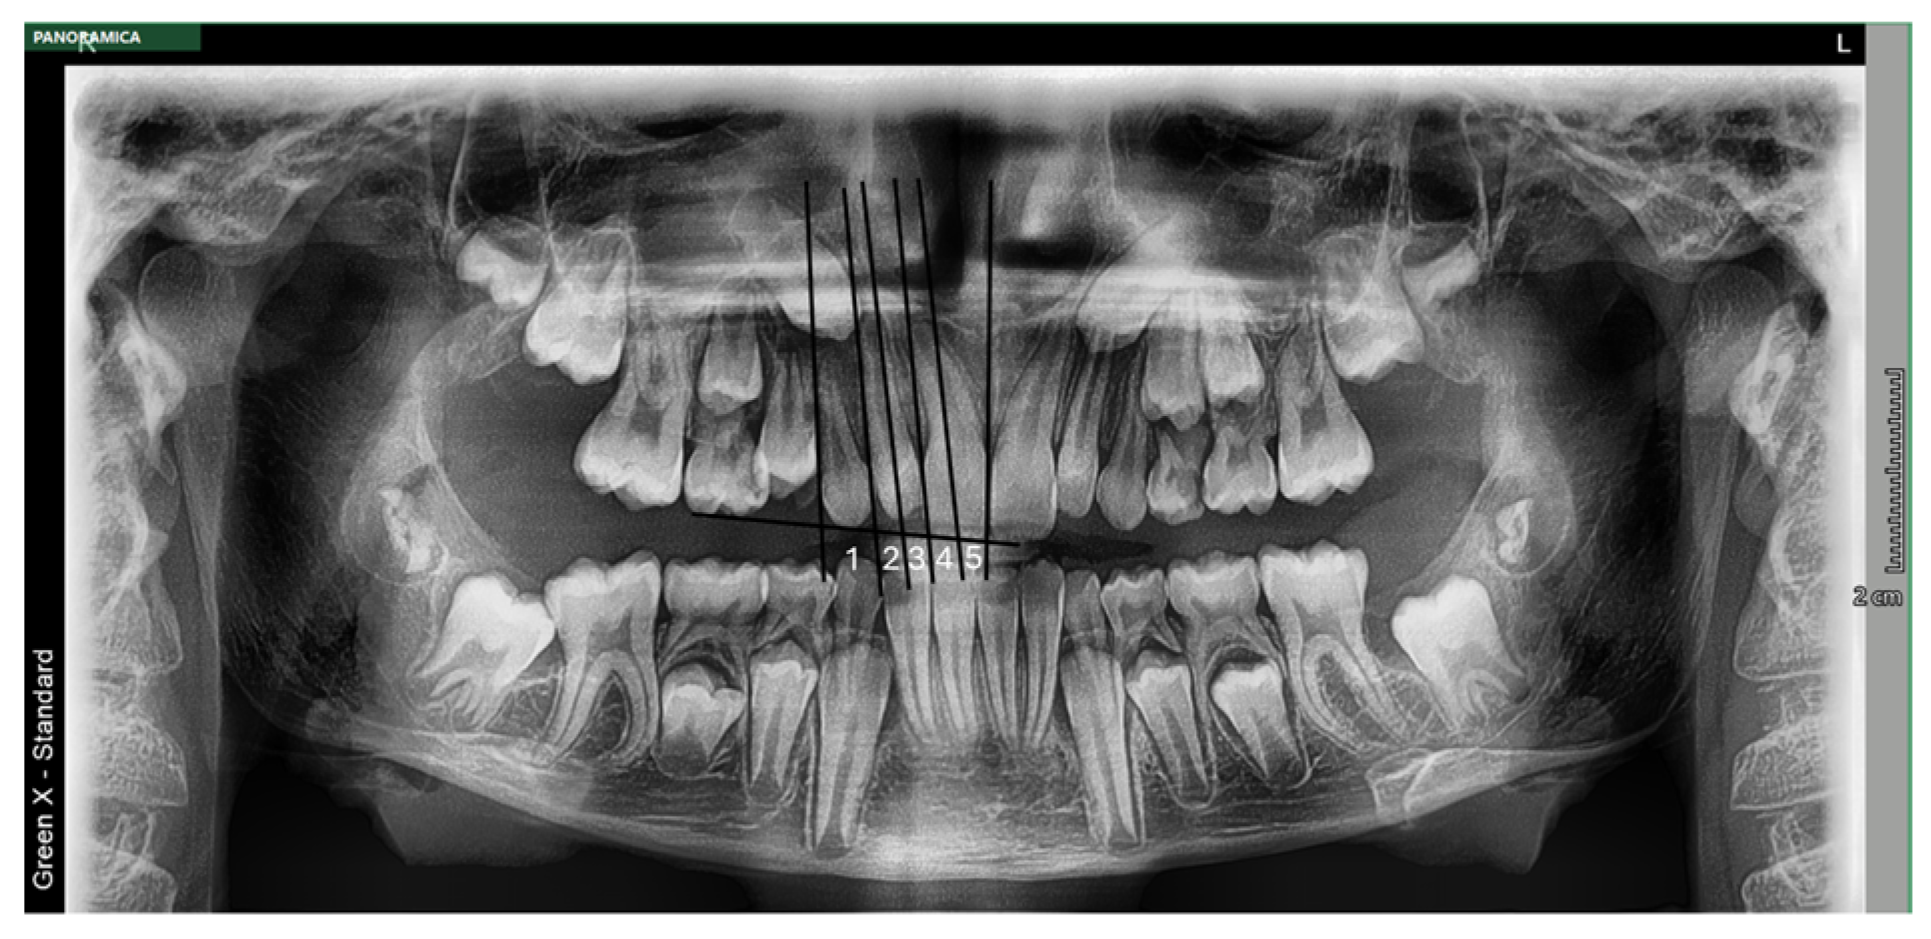

- Overlapping sectors (Sector I to IV): according to the “sectoral method” (EK/L method) adapted by Ericson and Kurol [16] and modified by Lindauer et al. (EK/L) [43], as described elsewhere [44]. According to three distal, central, and mesial lines drawn tangent to the contour of the root and crown of the adjacent permanent lateral incisor, the following four sectors were identified to locate the canine position. Sector I was located distally to the distal line, thus reflecting the position of the primary canine. Sector II corresponded to the area between the distal and central lines. Sector III identified the area from the central to mesial lines. Lastly, Sector IV was located mesially to the mesial line. Thus, the “sectoral method” was utilized to identify the mesiodistal position of the impacted permanent maxillary canine, based on the location of its cusp tip. Consequently, Sector I and Sector II were classified as “low/moderate risk of inclusion”, while Sector III and Sector IV as “high risk of inclusion”. This decision was also supported by the study by Warford et al. [45].